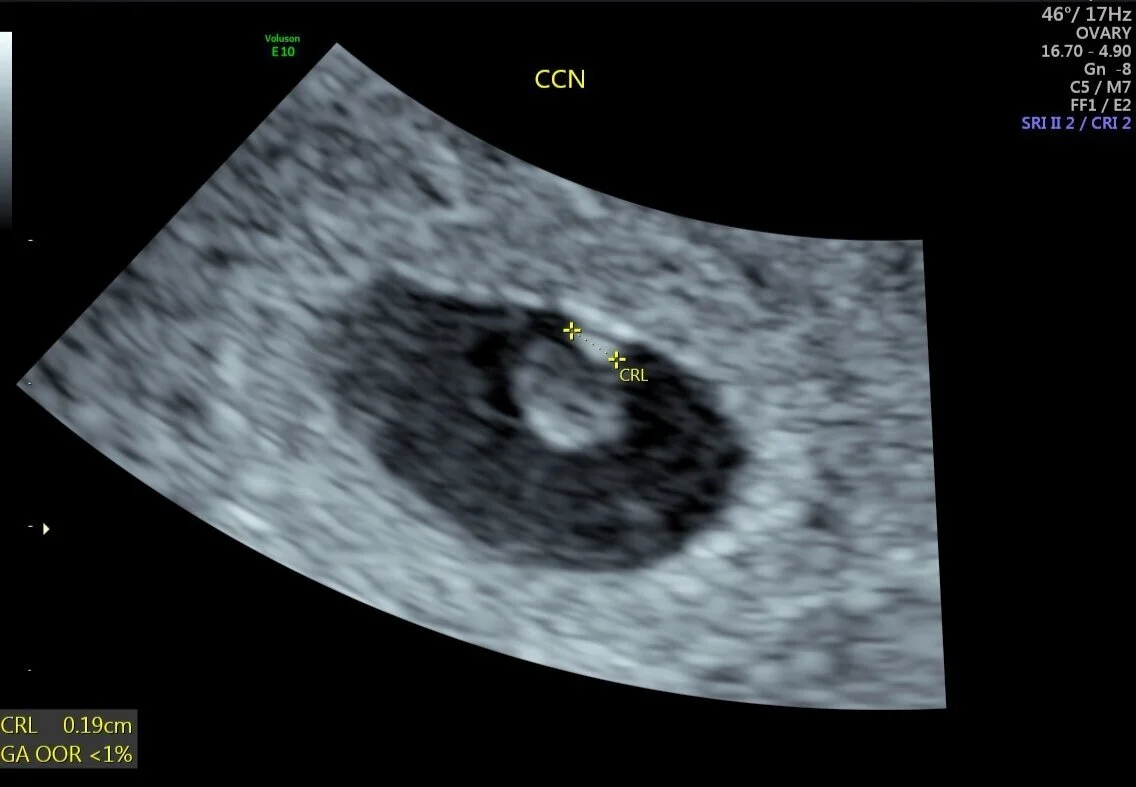

Ecografia Transvaginal A Saco Gestacional De 0 4 Cm Y Una Longitud Download Scientific Diagram